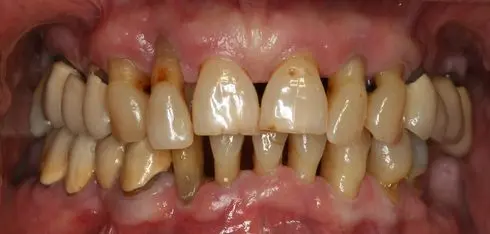

Bolest parodonta (parodontoza, parodontitis) najčešća je bolest suvremenog svijeta poslije karijesa. Danas sve više i više pacijenata dolazi u ordinaciju upravo radi tog problema. Parodontoza ne bira spol niti godine te je iz tog razloga vrlo bitno na vrijeme prepoznati simptome i krenuti u proces liječenja. Činjenica je da nakon 40. godine života više ljudi izgubi zube zbog parodontoze nego karijesa.

Ranim stadijem bolesti parodonta zvanog gingivitis oštećuje se površinski dio tkiva koji je današnjim metodama liječenja parodonta moguće sanirati na vrijeme. Taj stadij se očituje simptomima kao što su preosjetljivost zubnog mesa, naticanje gingive, stvaranje parodontnih džepova i podizanje zubnog mesa koje vodi laganom ogoljenju korijena zuba. Ako se početni stadij bolesti parodonta ne liječi, bolest može uznapredovati do kasnijeg stadija parodontoze koja sa sobom nosi klimanje i posljedično ispadanje zubi.

Kod stupnja uznapredovalosti gdje je već došlo do klimanja zubi potrebno je zube učvrstiti mostovima odnosno povezanim krunicama koje daju potporu strukturi zuba i time sprječavaju prerano ispadanje zuba. Kada dođe do velikog ogoljenja zubnog korijena na više zubi ili u cijeloj čeljusti, zubi se kreću klimati i zato je ogoljeli dio korijena potrebno zaštiti protetskim nadomjestcima kao što su krunice. Kada dolazi do nestanka tkiva gingive i ogoljenja zubnog korijena moguće je napraviti presađivanje gingive sa sluznice usne šupljine. Presađivanjem gingive sprječava se daljnje propadanje zubi i zubnog mesa.